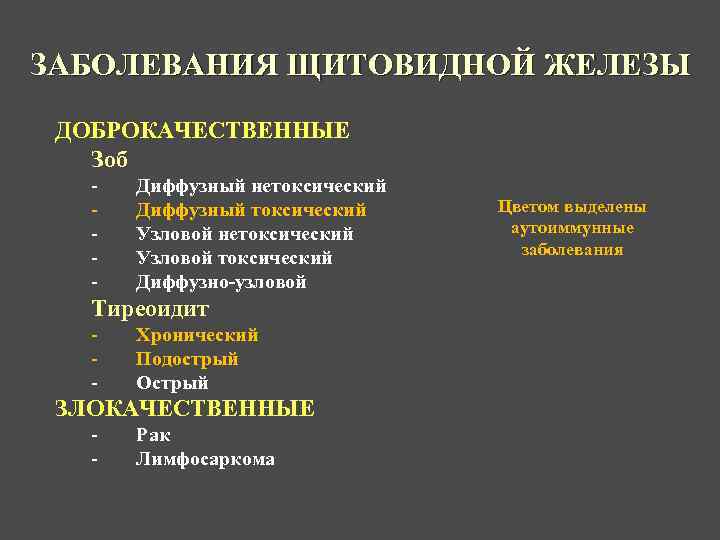

ЗАБОЛЕВАНИЯ ЩИТОВИДНОЙ ЖЕЛЕЗЫ ДОБРОКАЧЕСТВЕННЫЕ Зоб - Диффузный нетоксический Диффузный токсический Узловой нетоксический Узловой токсический Диффузно-узловой Тиреоидит - Хронический Подострый Острый ЗЛОКАЧЕСТВЕННЫЕ - Рак Лимфосаркома Цветом выделены аутоиммунные заболевания